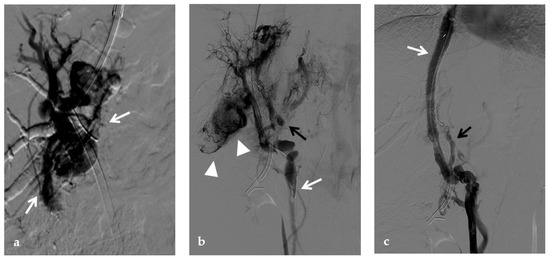

Figure 11.

Anteroposterior view of a percutaneous transmesenteric portography imaging series of an acute complete portal vein thrombosis occurred early after pediatric split-liver transplantation in a 1-year-old female with biliary atresia. (a) Superior mesenteric portography performed through a surgically-placed transmesenteric sheath (white arrow) shows total occlusion of the main portal vein and its intrahepatic branches, with opacification of several portosystemic varices (black arrows). (b) Superior mesenteric portography shows effective embolization of the portosystemic shunts to reduce the flow-steal phenomenon. A mixture of N-butyl cyanoacrylate and iodized oil and metallic microcoils (arrows) were used. (c) Portography image shows angioplasty with a 5-mm non-compliant balloon catheter performed on a stiff guidewire advanced through the common portal vein (white arrow). Note the spontaneous remaining opacification caused by the mixture of N-butyl cyanoacrylate and iodized oil (black arrows). (d) Final superior mesenteric portography shows restored opacification of the portal vein anastomosis, the umbilical recess of the portal vein (black arrow) and the intrahepatic segment 2 and segment 3 branches (white arrows), with no contrast filling of the portosystemic shunts.